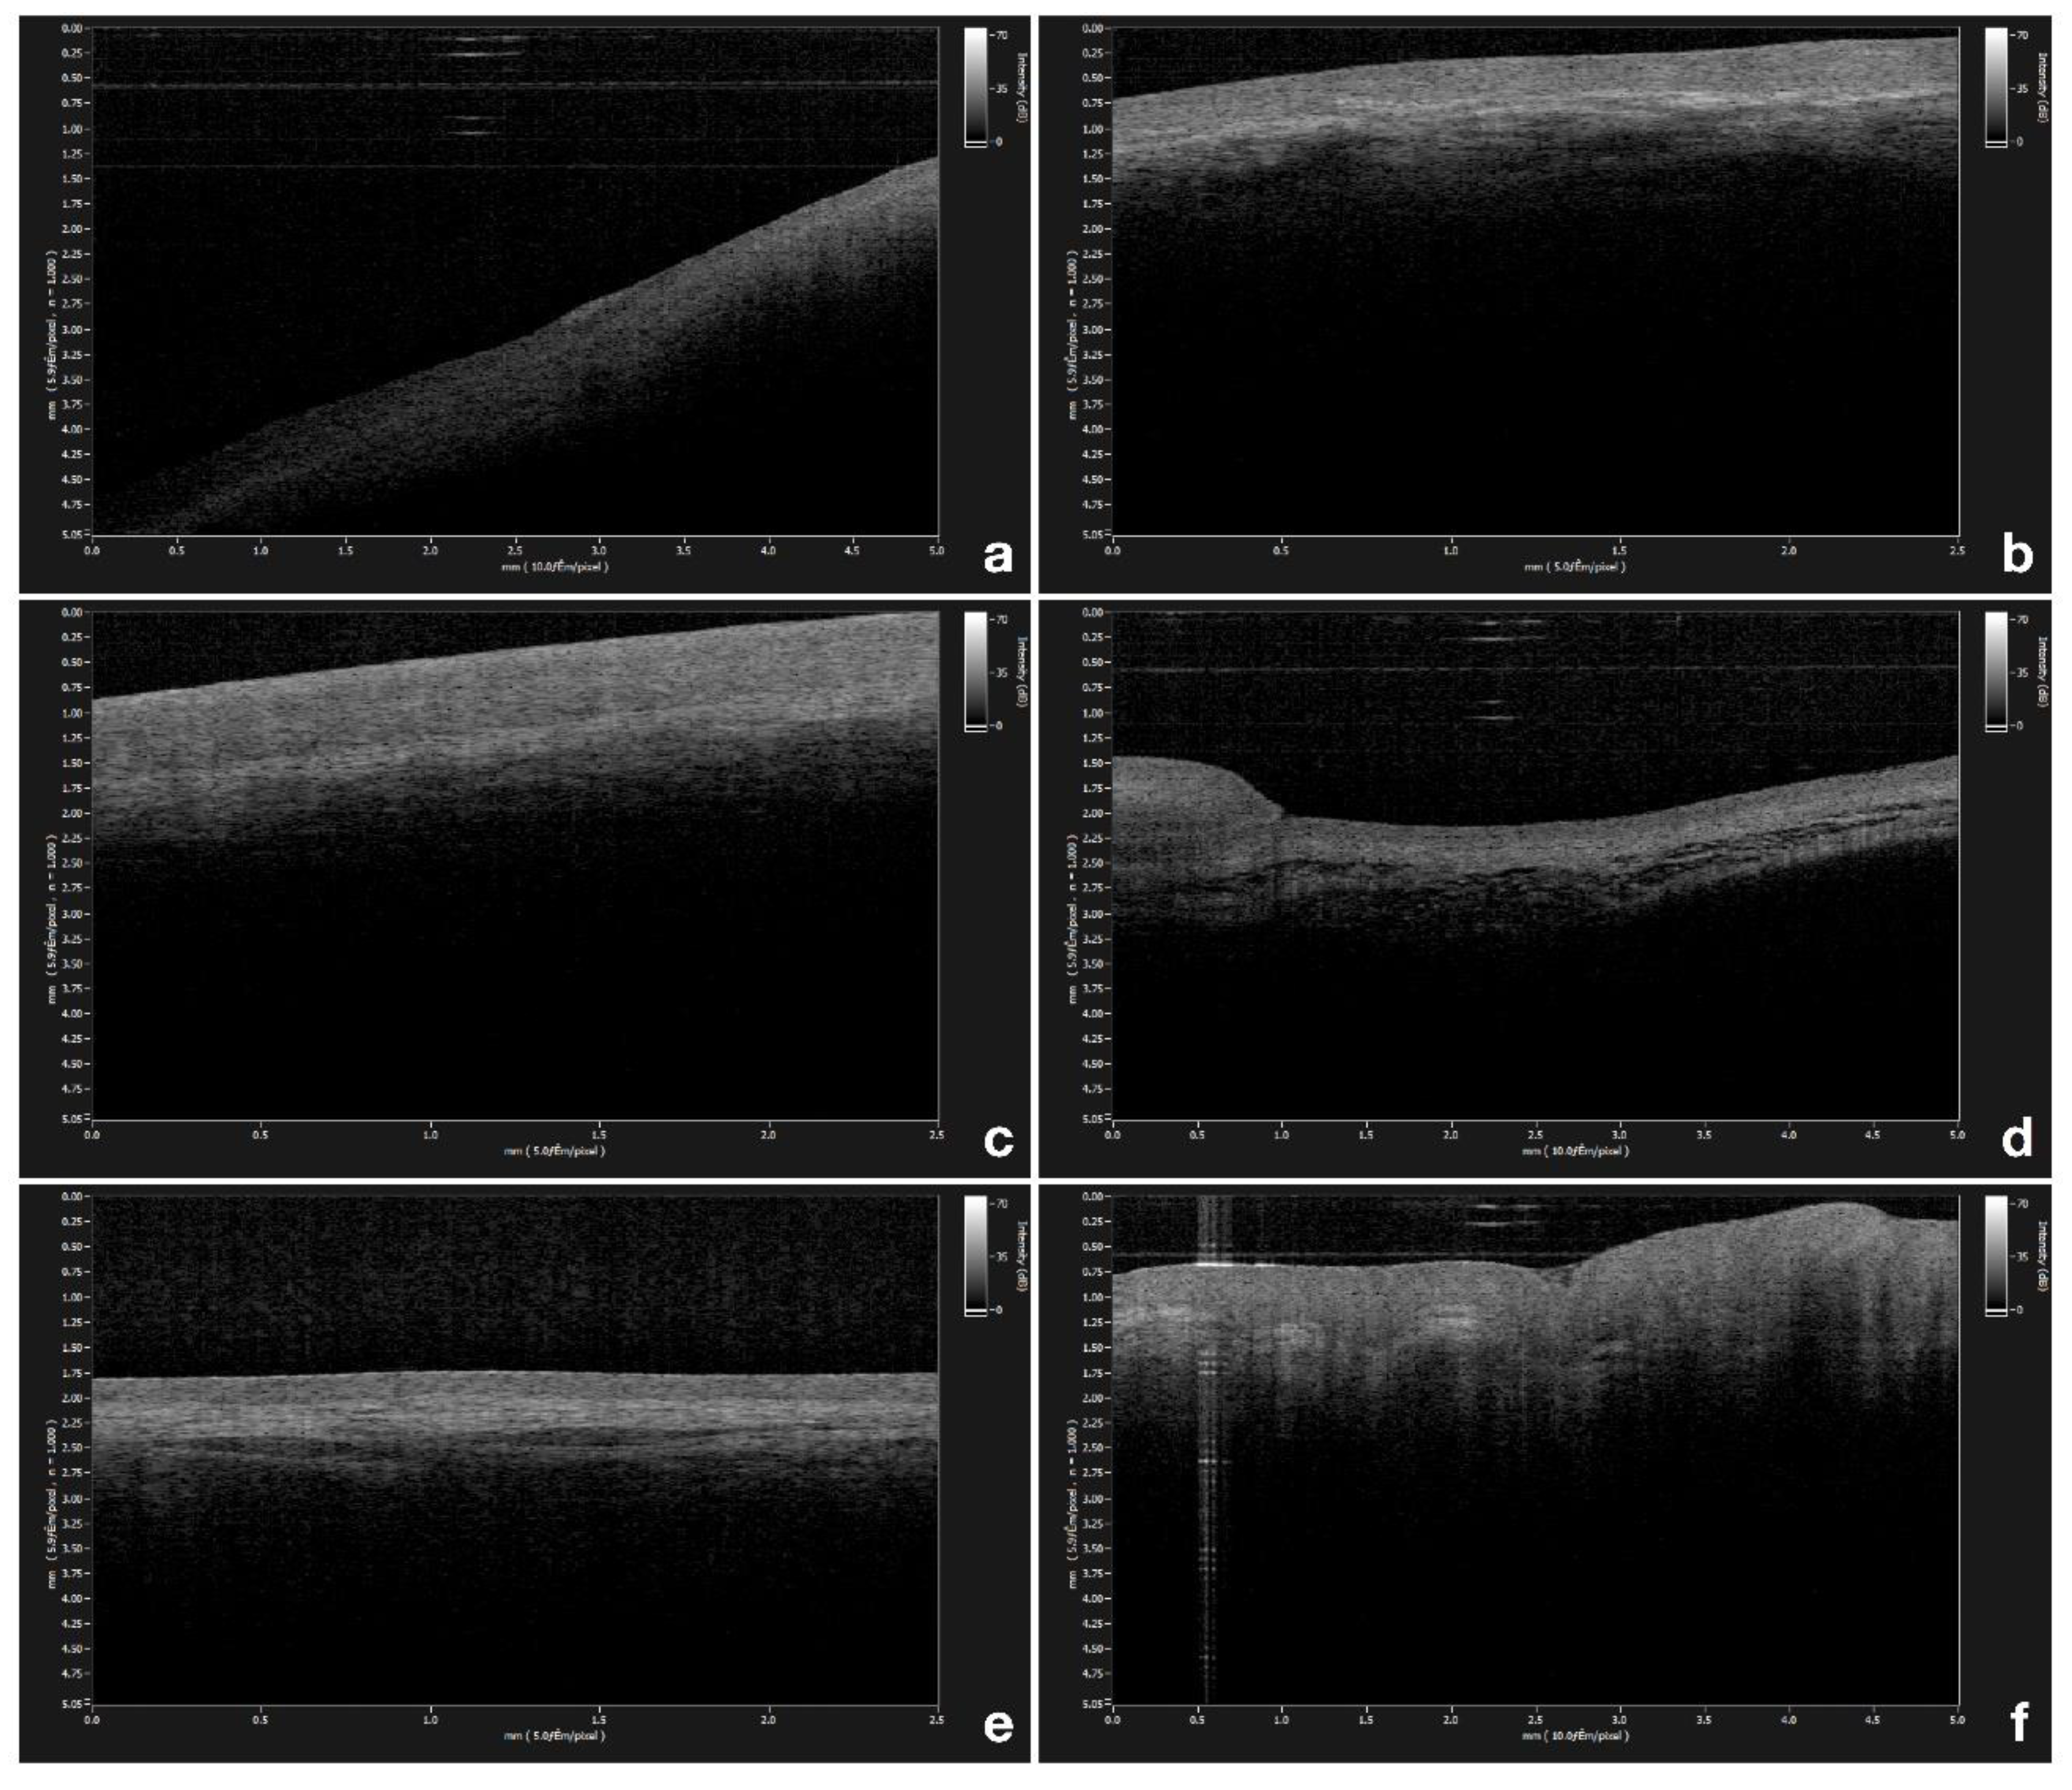

OCT measurements of epithelial thickness were performed at the exact same site in all patients, bilaterally at 6 different locations within the oral cavity, namely, the gingiva (Figure 1a), the labial mucosa (Figure 1b), the buccal mucosa (Figure 1c), the ventral surface of the tongue (Figure 1d), the floor of the mouth (Figure 1e), and the tongue dorsum (Figure 1f). Three repeated scans were performed in the same location.

Figure 1. (a) Optical coherence tomography (OCT) image of healthy gingiva; (b) OCT image of healthy labial mucosa; (c) OCT image of healthy buccal mucosa; (d) OCT image of healthy ventral surface of the tongue; (e) OCT image of healthy floor of the mouth; (f) OCT image of healthy tongue dorsum.

Through the OCT examination of a healthy buccal mucosa, it was possible to clearly establish the stratified squamous epithelium (SS) along the mucosal surface, underlying the lamina propria (LP), and the transition between these tissues along the basement membrane (BM) boundary.

The appearance of these tissues is strictly related to their optical density and scattering properties; that is why the lower optical density of buccal mucosa epithelium is darker, as evident in a lower signal intensity. Conversely, the optically denser LP appears brighter than the BM one, caused by a higher signal intensity. The lower contrast is a typical characteristic of a keratinized epithelium. Moreover, there are very few differences between the OCT image of the gingival mucosa and its own lamina (LP) at a depth of 285.04 ± 32.98 µm.